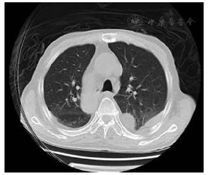

影像学检查:心脏彩超未见赘生物。甲状腺彩超:甲状腺实质回声欠均匀。浅表淋巴结彩超:双侧腹股沟多发肿大淋巴结(考虑反应性)、双侧颈部淋巴结未见明显异常、双侧腋下多发肿大淋巴结(考虑反应性)。腹部彩超:胆囊多发结石、胆囊内胆汁淤积。双下肢静脉彩超:双下肢深静脉血流通畅。泌尿系彩超:双肾囊肿、膀胱粘膜稍厚欠光滑、前列腺钙化斑。骨密度:低骨量。胸部CT:(1)双肺炎性病变;(2)双肺气肿,右下肺肺大泡;(3)左肺上叶陈旧性病变;(4)双侧胸膜增厚伴双侧胸腔积液;(5)心脏增大伴少量心包积液;(6)主动脉及冠状动脉硬化(图4)。胸腔积液超声:双侧胸腔积液(不宜定位)。全腹部CT:(1)胆囊多发结石;(2)右肾低密度影;(3)前列腺增大;(4)盆腔少量积液;(5)动脉硬化;(6)心包及双侧胸腔积液。

经上述抗感染治疗共8周后,患者未再发热,精神症状未再反复,皮肤破溃处基本愈合,无颈抵抗。实验室指标复查,血常规、肝肾功能电解质、葡萄糖、凝血常规等均未见明显异常,CRP 0.821 mg/dl,PCT 0.093 ng/ml,ESR 55 mm/h,血培养阴性。胸部CT显示炎症及胸腔积液较前明显好转,穿刺部位彩超显示感染灶吸收。出院后随访6个月,患者未再出现发热及精神症状等表现,复查血常规、炎症和生化指标等均在正常范围内。随访期间患者曾有右侧肢体无力,就诊当地医院,考虑急性脑梗死,对症治疗好转。